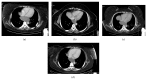

Neoadjuvant imatinib for gastrointestinal stromal tumours (GISTs) is increasingly used nowadays. As oesophagectomy is associated with high morbidity and mortality, a preoperative downsizing of an oesophageal GIST to limit the extent of resection would be ideal. Because these tumours are rare and neoadjuvant treatment with imatinib is recent, there is limited literature available regarding neoadjuvant administration of imatinib in patients with oesophageal GISTs. A 50-year-old woman presented with total dysphagia. An upper endoscopy and biopsy revealed a large submucosal KIT-positive GIST obstructing the mid oesophagus. CT confirmed a lesion measuring 99 mm × 50 mm × 104 mm. Because the size and location of the tumour increased the risk of intraoperative rupture, it was decided to administer preoperative imatinib. The patient had an excellent clinical and radiological response. Her dysphagia gradually resolved and the follow-up CT scans of the first 10 months showed a gradually reducing tumour size to 54 mm × 33 mm × 42 mm. The patient underwent an uneventful laparoscopic-assisted Ivor-Lewis oesophagectomy. Postoperatively, the patient continued with adjuvant imatinib. At the last follow-up, 1 year from operation and 38 months from the diagnosis, the patient is disease free.